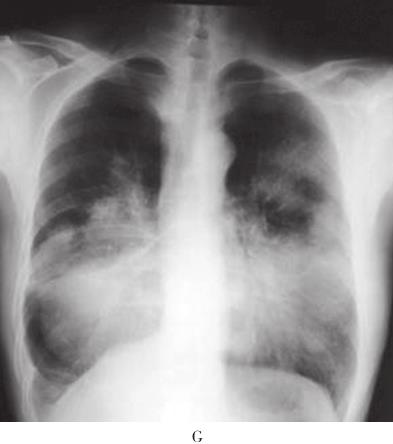

患者,男,56岁,因“活动后气短4年,加重3周”于2010年10月12日入院。入院前4年无诱因出现活动后气短,吸气时明显。3年前当地医院胸部CT检查示:双肺野内多个大小不等团片状密度增高影(图1A、B)。支气管镜下见:左上叶开口、右上叶开口及右下叶基底段开口处黏膜充血肿胀,管腔狭窄。支气管镜活检病理显示有大量淋巴细胞浸润。抗感染治疗后症状稍缓解。入院前1年上述症状加重,胸部CT示:双肺多发结节状、团块状病灶(图1C、D)。CT引导下肺穿刺活检病理示有大量淋巴细胞及浆细胞浸润,血管扩张充血,炎性渗出。诊断为双肺多发炎性肉芽肿,具体治疗不详。入院前2个月出现反复右侧鼻腔少量出血。入院前3周活动后气短加重,拟诊“双肺多发阴影性质待查”收入院。病来无发热、盗汗、咯血、胸痛、皮疹、关节痛。患者4年间多次在当地医院就诊,“怀疑肺结核、肺真菌病及肉芽肿病”,经验采用抗结核、抗真菌等治疗,具体治疗方案及疗程患者及家属叙述不清,疗效不佳。入院前半年,出现乏力、食欲下降,体重减轻4~5kg。

图1 胸部CT

A、B:2007年4月胸部CT示双肺野内多个大小不等团片状高密度.C、D:2009年10月胸部CT示双肺多发结节样、团块样病.E~G:2010年10月胸部CT示右肺下叶巨大团块状类软组织密度影,双肺弥漫性团片状浸润及实变影,纵隔内多发肿大淋巴结;胸片示右下肺团块影,双肺多发结节影

入院后体格检查:一般情况佳,双侧颈部、锁骨上、腋窝、腹股沟可触及数枚肿大淋巴结,最大直径约2cm,质硬,边界清,活动度可,无压痛。双肺呼吸音粗,可闻及广泛哮鸣音。心、腹检查未见异常,肝脾肋下未触及。入院时实验室检查:血常规:WBC 5×109/L,HGB 111g/L,PLT 368×109/L;外周血涂片:白细胞正常范围,淋巴样浆细胞约占5%,成熟红细胞呈明显缗钱样排列,血小板增多。凝血功能检查:PT 15.2秒,凝血酶原活动度74%,APTT 43.9秒;血清肿瘤标志物及自身抗体谱检查阴性;PPD试验阴性;多次痰病原学检查阴性;C反应蛋白CRP)10.8mg/L;ESR 105mm/h;血β2微球蛋白44.9ng/L;血清总蛋白106g/L,血清白蛋白35g/L,白蛋白/球蛋白0.49。胸部X线示:右下肺团块影,双肺多发结节影。胸部CT示:右肺下叶巨大团块状类软组织密度影,双肺弥漫性团片状浸润及实变影、纵隔内多发肿大淋巴结图1E和F)。支气管镜:右上叶、右中叶、右下叶、左上叶、左下叶背段支气管开口黏膜充血水肿,可见不规则隆起,向腔内生长,触之易出血,表面光滑;右下叶、左上叶支气管开口完全闭塞;于右下叶开口行支气管黏膜活检。该患者有乏力、鼻黏膜出血倾向等高黏滞血症表现,血清总蛋白106g/L,血清白蛋白35g/L,提示患者存在血清球蛋白异常增多。遂继续查免疫球蛋白定量、血清蛋白电泳及骨髓穿刺活检。结果为:IgM 87.30g/L、IgA 0.73g/L、IgG 8.14g/L、κ轻链100g/L、λ轻链3.49g/L;血清蛋白电泳及免疫固定电泳显示M成分为IgM κ,尿本周蛋白阴性。骨髓形态学示:红系增生,分类以中晚幼红为主,可见巨变、类巨变、双核红,成熟红细胞呈明显缗钱样排列;淋巴样浆细胞多见,约占23%;骨髓瘤细胞约占6%。血清单克隆IgM升高,血清免疫固定电泳检出IgM κ,外周血及骨髓中淋巴样浆细胞增多,支气管黏膜、骨髓及淋巴结活检组织标本病理均提示淋巴细胞浸润,表达CD20、CD79α、CD138等B细胞免疫表型,且轻链呈限制性表达(表1)。支气管黏膜活检示均匀一致的小淋巴细胞弥漫浸润,结合免疫组化结果,符合黏膜相关淋巴组织结外边缘区B细胞淋巴瘤(MALToma)。患者既存在骨髓侵犯,又存在单克隆性IgM分泌,故诊断为华氏巨球蛋白血症(Waldenström macroglobulinemia,WM),肺部多发占位为华氏巨球蛋白血症肺部浸润,伴局部肺不张。